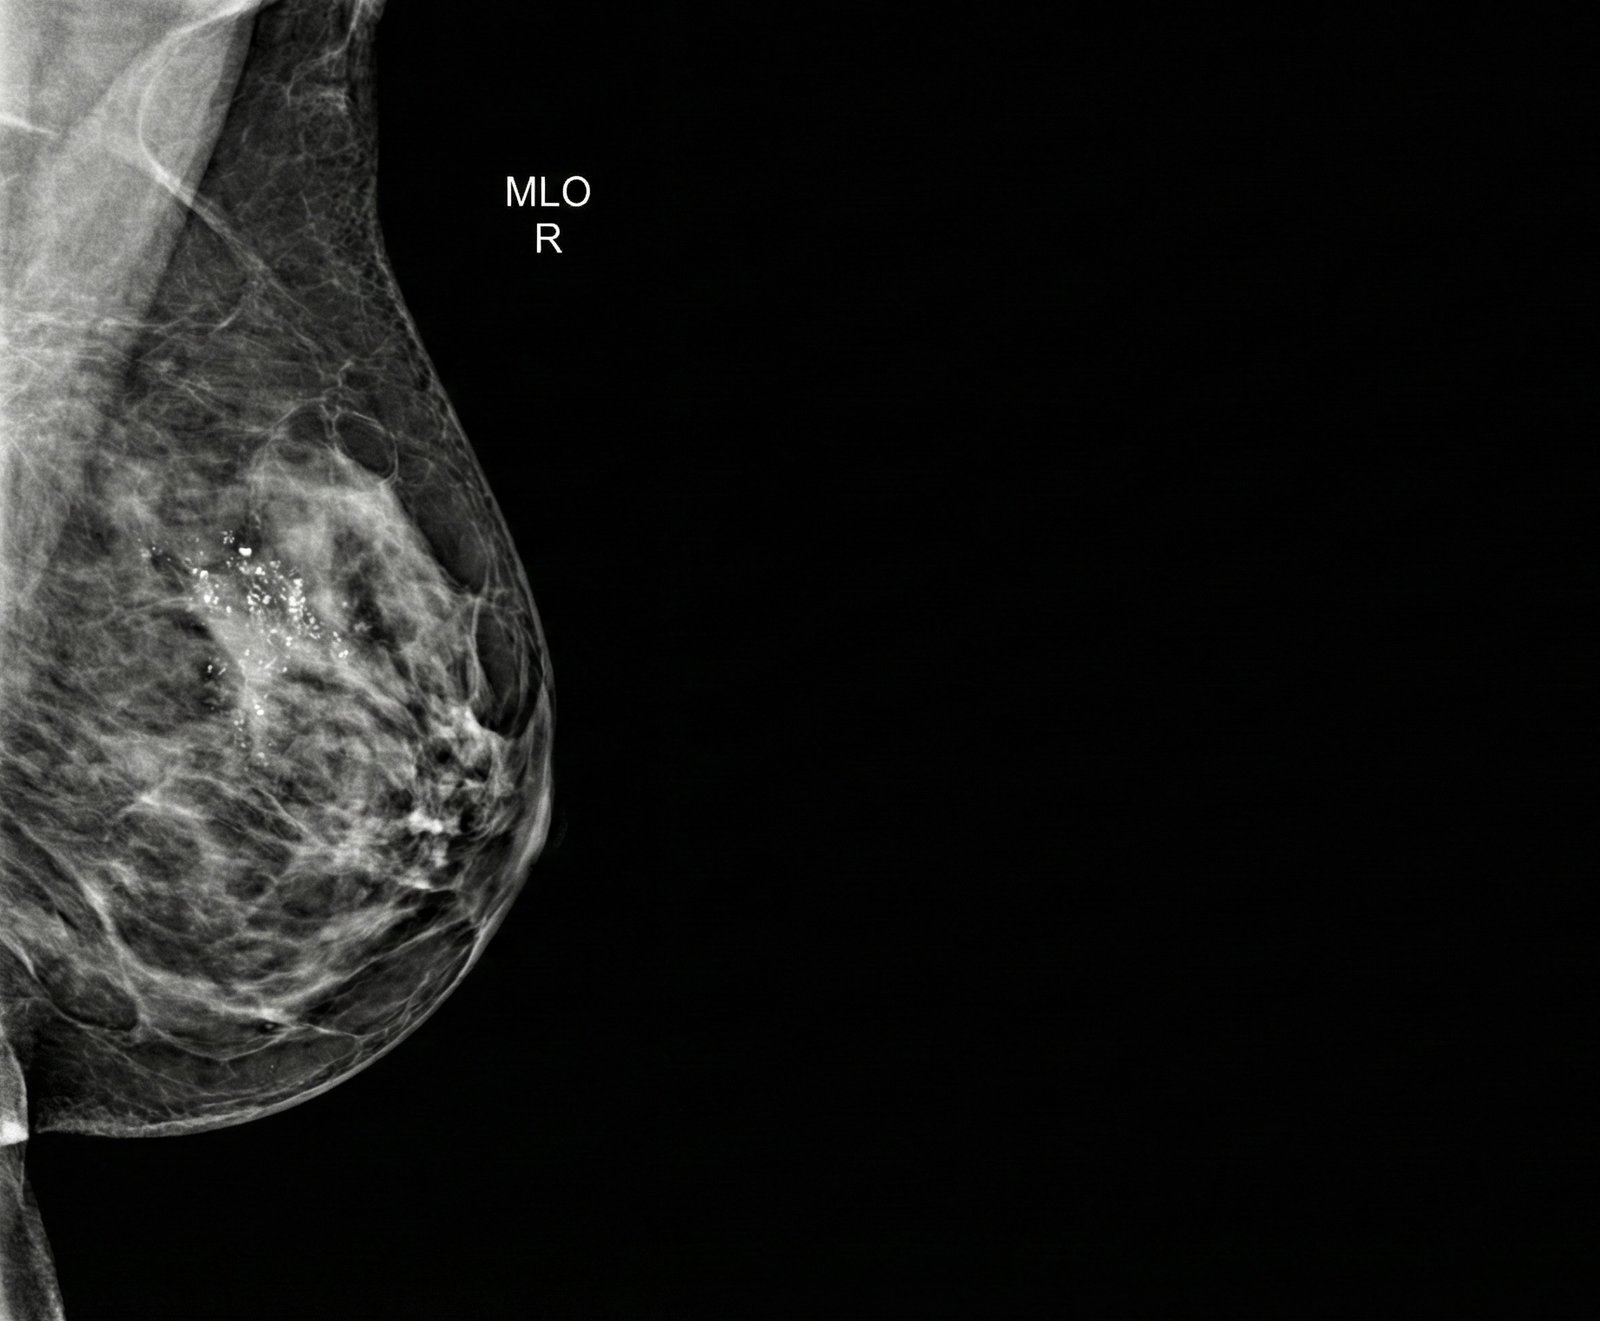

Nel linguaggio radiologico, con microcalcificazioni si indicano piccolissimi depositi di calcio all’interno del tessuto mammario, visibili alla mammografia come puntini bianchi, spesso raggruppati in piccole aree.

- Microcalcificazioni: puntini molto piccoli, spesso inferiori a mezzo millimetro, talvolta isolati, talvolta organizzati in gruppi o “cluster”. A seconda della forma (morfologia) e di come sono distribuite nel seno possono essere completamente benigni oppure sospetti.

Alcuni esempi di microcalcificazioni benigne sono quelle dovute a piccole cisti, secrezioni in dotti mammari, esiti fibrocistici o calcificazioni vascolari. Altre, con un aspetto più irregolare o distribuite lungo i dotti, possono invece essere correlate a lesioni cosiddette preneoplastiche o a forme iniziali di carcinoma, come il carcinoma duttale in situ (DCIS).

- Morfologia: microcalcificazioni rotondeggianti o “a tazza di tè” sono in genere benigne; forme sottili, lineari o ramificate, irregolari o “a chicchi di sale grosso” possono essere più sospette.

- Distribuzione: microcalcificazioni sparse un po’ ovunque nel seno hanno spesso significato benigno; se invece sono raggruppate in un’area limitata, oppure seguono il decorso di un dotto (distribuzione lineare o segmentaria), l’attenzione aumenta.

Se l’aspetto è considerato sospetto (per esempio microcalcificazioni fini, irregolari, lineari o ramificate, organizzate in cluster o con distribuzione segmentaria), la raccomandazione più frequente è eseguire una biopsia guidata dalla mammografia.

- Carcinoma duttale in situ (DCIS): è la forma più frequentemente associata a microcalcificazioni lineari, ramificate, finemente pleomorfe e organizzate in cluster o con distribuzione segmentaria.